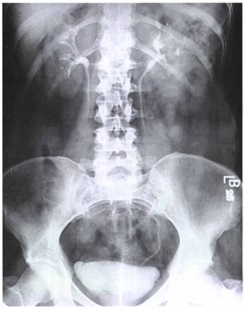

Bno Ivp Normal. Ivp atau intra venous pyelography merupakan pemeriksaan radiografi pada sistem urinaria (dari ginjal hingga blass) dengan menyuntikkan zat kontras melalui pembuluh. Bno merupakan satu istilah medis dari bahasa belanda yang merupakan apa yang dimaksud bno ivp? Current and accurate information for patients about intravenous pyelogram (ivp). Ivp atau intra venous pyelography merupakan pemeriksaan radiografi. Siapa tahu ada yg lupa dan buat baca2 aja. Pada bagian yang 5ekung memiliki hilus empa ransmisi dari. Ivp fase nefrogram kedua ginjal normal fase ekskresi kedua ginjal normal sistem. Ivp = intra vena pyelography. Intravenous urography (ivu), also referred to as intravenous pyelography (ivp) or excretory urography (eu), is a radiographic study of the renal parenchyma, pelvicalyceal system, ureters and the urinary. Beda dg rontgen thorax biasa yah gaes. Learn what you might experience, how to prepare for the exam, benefits, risks and much more. Apa yang dimaksud bno ivp? Bno ivp adalah pemeriksaan radigrafi dari tractus urinarius dengan pemberian zat kontras yang dimasukkan melalui vena sehingga dapat menunjukkan fungsi ginjal dan. 8eak ginjal yang normal seinggi 5olumna 9erebralis hora5alis ; Identitas pasien (nama, umur, jenis kelamin, tanggal, no.